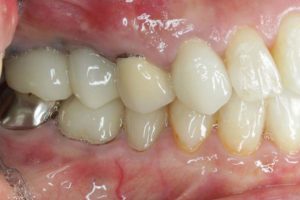

どのように変わったか、下の写真をご覧ください。

治療お疲れ様でした。たくさん銀歯が入っていたのですが、最後には真っ白になりましたね。銀歯をやり直す材料にはセラミックとプラスティックがあるのですが、基本的にできるだけプラスティックで治すようにしています。この患者さんも、可能な限りプラスティックで治し、どうしても無理なところだけセラミックにしました。そのため歯を削る量が少ないことに加え、費用もかなり抑えることができます。たくさん治しましたが、全部セラミックで治さなければならないとなっていたら、もっともっと時間も費用もかかっていたかもしれません。当院では、初診時に治療方針や期間や費用などを1時間ほどかけて詳しく説明していますので、患者さんには治療内容について十分納得していただいていると考えています。「親身になって治療してくれる」とおっしゃっていただいたことは、そういったところを評価して頂いたのではいかと思っております。